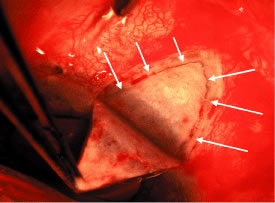

To facilitate a posterior incision, a superior rectus bridle suture may

is not within the tissue to be cut by the scissors. Tenon's capsule, with its conjunctiva, is spread anteriorly over the

cornea to give the best view possible of the corneal scleral sulcus. In

almost all instances, there is a thin layer of episclera remaining. This

layer is grasped and elevated forcibly, permitting development

of a 2 × 2-mm buttonhole, through which the bare sclera is easily

visible. This episcleral tissue is markedly adherent. The buttonhole

should be extended approximately 5 mm temporally and laterally. The

forceps are used to grasp the edge of this deep episcleral tissue, and

pull it anteriorly and inferiorly, so the surgeon can clean down to bare

sclera anteriorly to the corneoscleral sulcus. The sulcus is not readily

visible until the episcleral tissue has been reflected from it. In

fact, it probably is the single most important landmark with regard

to filtration surgery. As seen in Figure 4, the conjunctiva inserts just anteriorly to the corneoscleral sulcus. Dissection